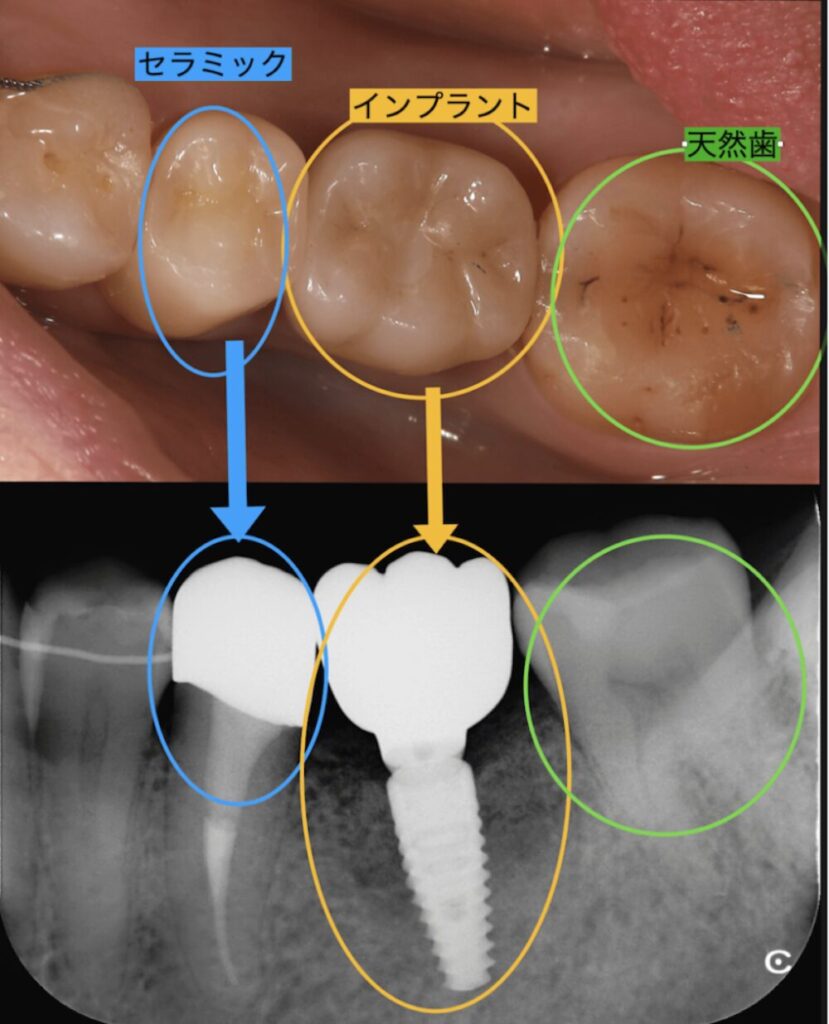

実際の症例

神経の治療をした自分の歯の根に被せるセラミックとインプラントの上部構造のセラミック、そして自分の歯である天然歯は外から見るとほとんど差は感じられません。しかし、レントゲンで診てみると構造は全く違うものだとわかります。

この三つは噛む力はほとんど変わりません。よって噛む力を均等に分散できるので良く噛めて長持ちするのです。入れ歯は歯茎の上に乗せて機能するので、噛んだ時に歯茎が凹み噛む力が逃げてしまうのです。

したがって自分の歯のように噛めにはインプラントが最適であることがわかります。